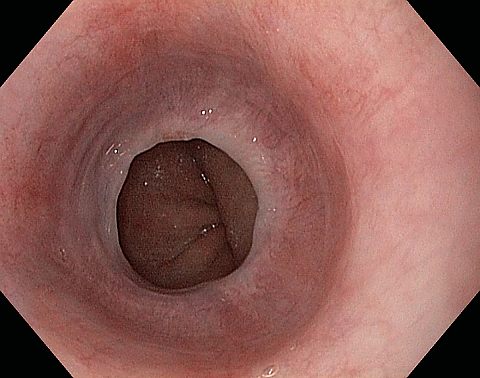

Reflux oesophagitis grade D according to the Los Angeles classification